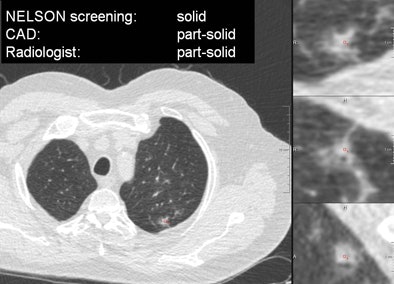

VIENNA - Taking a step beyond lung nodule detection schemes evaluated in previous studies, researchers from the Netherlands have developed an automated method of characterizing nodules as solid, part-solid, or nonsolid, pointing the way to different patient management paths, according to a presentation at ECR 2013.

In results from more than 100 patients who underwent lung cancer screening with CT as part of the Nederlands-Leuvens Longkanker Screenings Onderzoek (NELSON) lung cancer screening trial, researchers from Radboud University Nijmegen Medical Centre in the Netherlands and several other institutions showed that their automated computer-aided detection (CAD) scheme for characterizing nodule types according to Fleischner Society criteria was nearly as accurate as the findings of an expert thoracic radiologist -- who despite his experience, expressed his own doubts about his ability to classify nodules correctly in every case.

"Now we have guidelines for solid nodules, for subsolid nodules, and the guidelines for subsolid nodules also differentiate between part-solid and nonsolid nodules," Jacobs said. "Classifying nodules in these three categories is crucial for patient management. The purpose of this study was to develop a CAD tool to do this automatically ... and to compare the performance of our CAD tool to an experienced thoracic radiologist on a large dataset obtained from a screening database."

The characterization scheme is initiated by the user inputting a seed point in the center of the nodule on the CT image. Then a volumetric segmentation algorithm is applied using different parameter settings to segment the complete nodule, the ground-glass components, and the solid core, Jacobs said. Each segmentation computes volumetric features to describe part of the nodule, and then a supervised classifier is applied to classify the candidates as solid, part-solid, or nonsolid.

"For each segmentation, it computes volume, mass, average density, the fifth percentile, and the 95th percentile of densities inside the segmentation," he said. All features are collected, and a supervised classifier, trained with examples, is used to classify the candidates into one of the three categories.